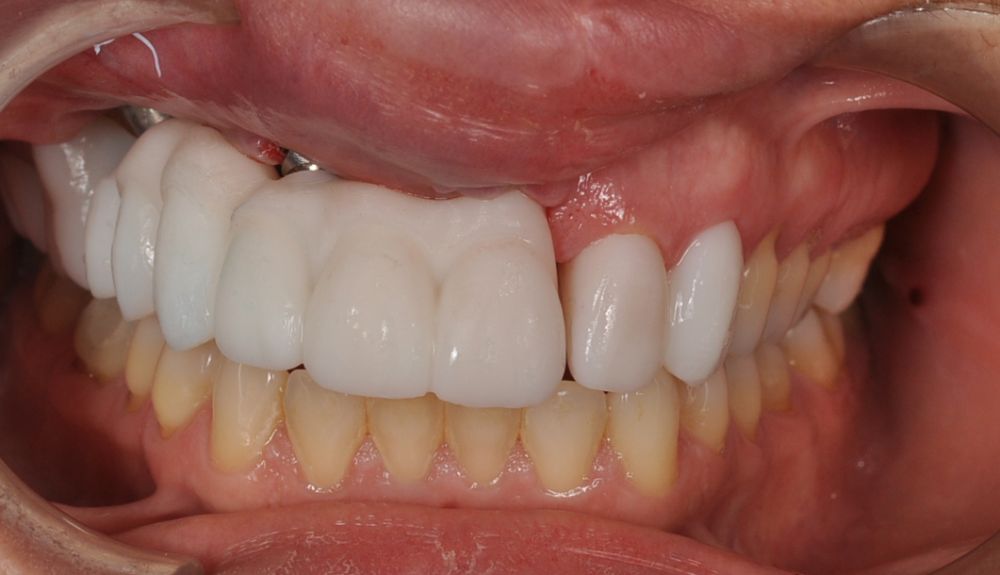

Para la fabricación de las estructuras, se eligió el óxido de zirconio monolítico como material restaurador sobre interfases metálicas en el puente implantosoportado, y coronas de óxido de zirconio monolítico en los dientes tallados previamente (1.7, 1.6, 2.2 y 2.3). Se tomaron impresiones de cubeta abierta con silicona de adición pesada y fluida (Zhermack Elite HD, Gmbh). Se realizó una prueba de pasividad analógica y el resto del proceso se confeccionó de manera digital, por lo que se hicieron pruebas estéticas de dientes impresas en 3D sobre interfases metálicas, para hacer todos los ajustes de función y estética previos al fresado del zirconio monolítico (Figuras 11, 12 y 13).

El día de la colocación de las estructuras, se arenó el interior de las coronas dentosoportadas con óxido de aluminio de 50 m y fueron cementadas con cemento de resina Multilink Ò. El puente implantosoportado se atornilló al torque indicado (20Nw) (Figuras 14, 15, 16 y 17).